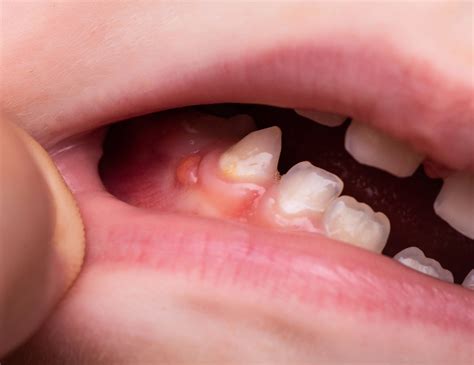

Una fístula dental es un pequeño canal que se forma desde la zona infectada del diente, que suele coincidir con el ápice de la raíz, hasta la superficie exterior de la encía. La fístula dental tiene el aspecto de una ampolla llena de pus en la boca, similar a un grano de pus. El pasaje actúa como depósito de pus y a medida que se llena, se forma una pequeña protuberancia en forma de grano cerca de las encías.

Al principio, las encías se inflaman ligeramente y enrojecen. Al principio, la zona afectada se hincha. Las encías se enrojecen y hay una sensación de tensión en el diente. A continuación, se forma una ampolla en la encía, encima o debajo del diente afectado, que se llena de pus a medida que avanza. La fístula al aparecer se presenta normalmente en la encía, en la cima superior del diente. Se trata, como bien indicábamos, de un bulto con pus producido por diferentes razones.